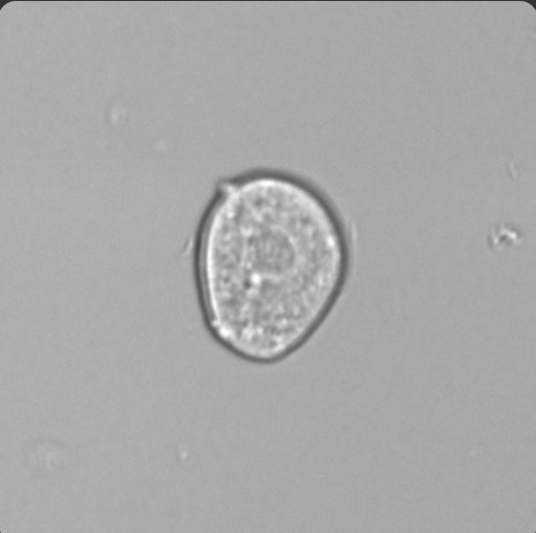

Red Blood Cells

Smaller than WBCs

Dimorphic RBCs= Problems with filtration membrane

Ghost cells- RBCs in alkaline urine (Alkaline urine causes cells to lyse)

Acetic acid- used to distinguish RBCs and Yeast, RBCs will lyse